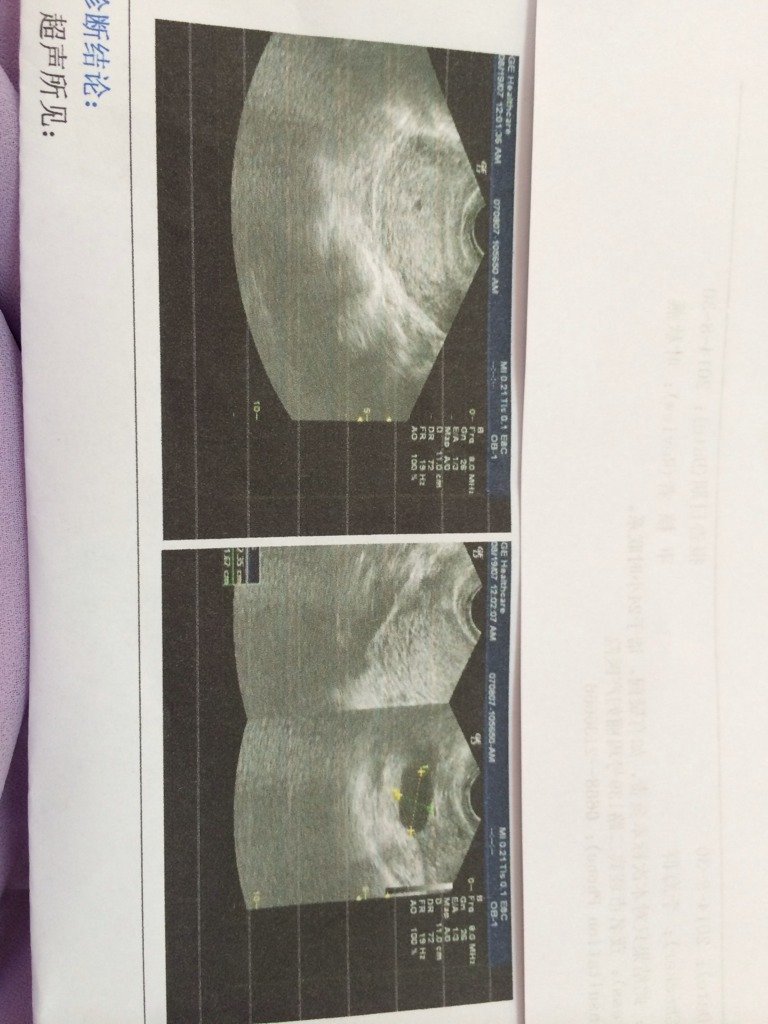

我都停经十天了,为什么今天来照这个,我觉得什么都不太懂,这里要是有医生懂的话,帮我看看这个到底是什 我都停经十天了,为什么今天来照这个,我觉得什么都不太懂,这里要是有医生懂的话,帮我看看这个到底是什么回事?谢谢。 点击展开 我的bb 2014-08-30 10:25 为您推荐: 其他回答 应该有写内容的吧 y986691628 2014-08-30 16:13 b超吧!看你是不是怀孕 单凯铎 2014-08-30 10:36 您好,您这种情况应该是怀孕了,B超报告中的黑色的椭圆形阴影就是孕囊 衷喜明2 2014-08-30 10:27 相关问题 这是我今天检查的我看不懂,问医生她也不耐烦,麻烦哪位懂的帮我看看宝宝现在有几斤了,我预产期是7月2